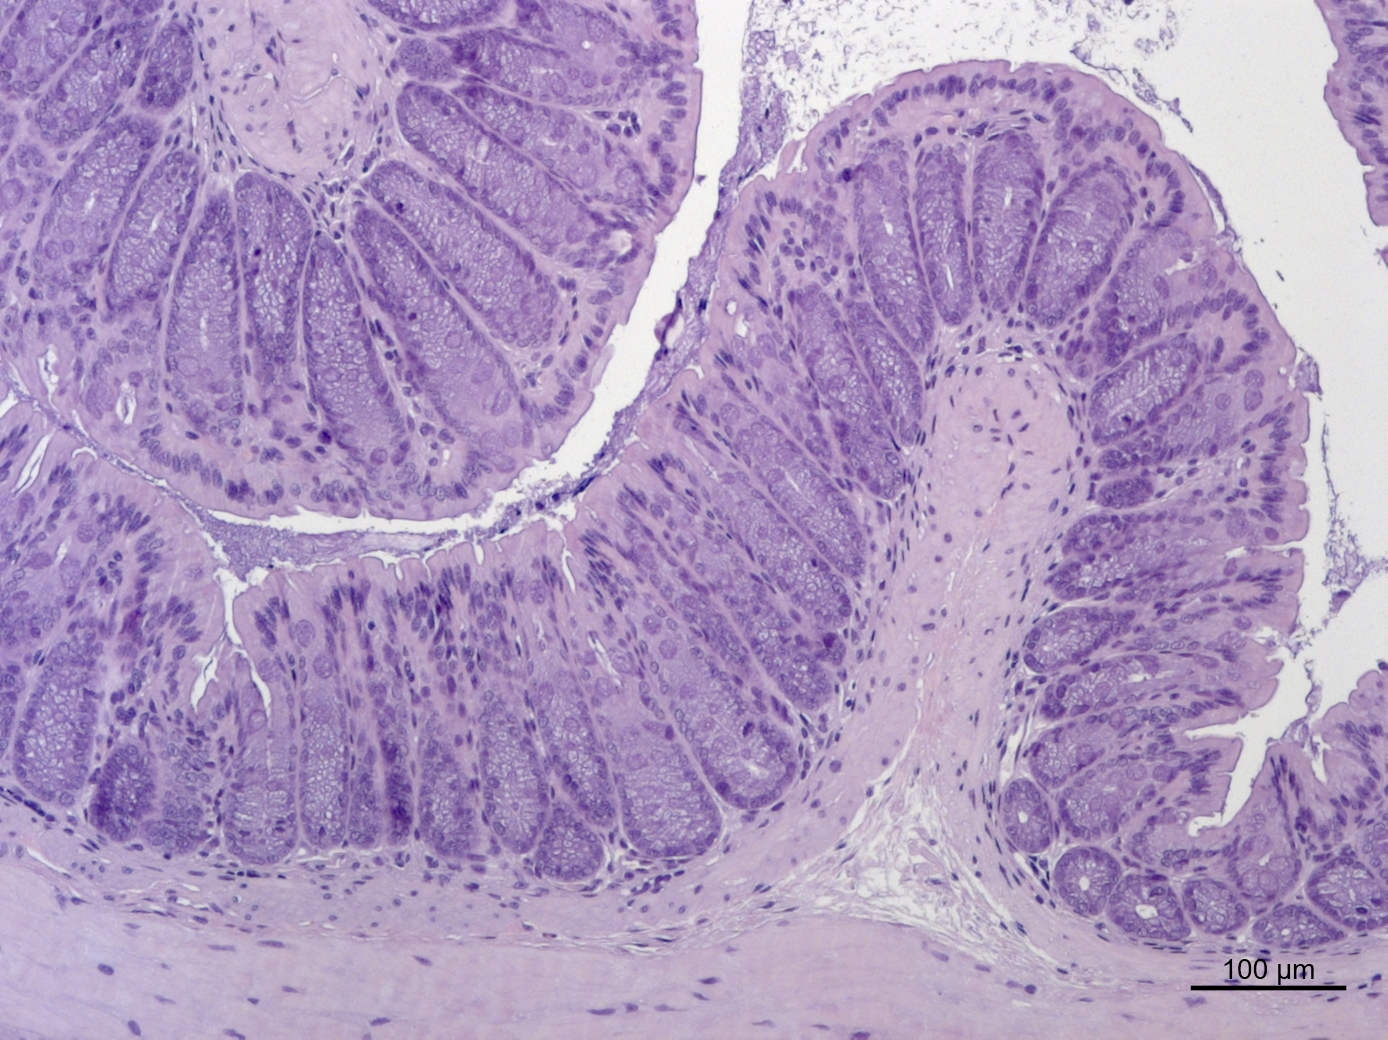

© Anja Kühl, Charité

Das Bild zeigt Darmgewebe aus einem Mausmodell für die erworbene generalisierte Lipodystrophie. Das Gewebe blieb auch nach der Behandlung mit einer Chemikalie, die normalerweise eine Darmentzündung auslöst, intakt.